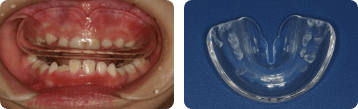

ムーシールド

反対咬合の早期初期治療に用いる装置で、3歳頃から使⽤できます。⾆を正しい位置づけができるように持ち上げ、上顎の成長を促し、成長を妨げる上口唇の強い力を排除します。主に就寝時に装着することで、舌と口唇の筋肉のバランスを保ち、咬み合わせの改善を促します。

拡大床(スクリュー)

週に1回ねじを回し、顎の幅を拡げます。自分ではずすことができ、日中や夜間に使用します。

拡大装置

拡大装置は、自分ではずせない固定式の装置です。